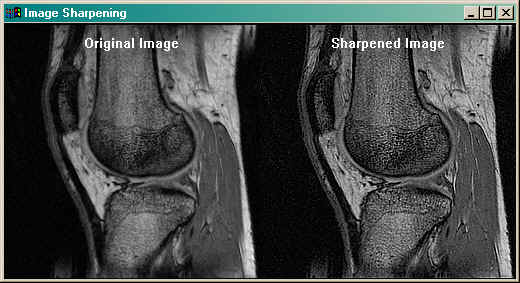

The purpose of this program is to sharpen an image with a Laplacian filter. Laplacian filters identify

edges in images. In sharpening, these edges are added back to the image to produce a "sharpening" effect.

For a more complete description of the method use, see the article

Image Sharpening with a Laplacian Kernel.